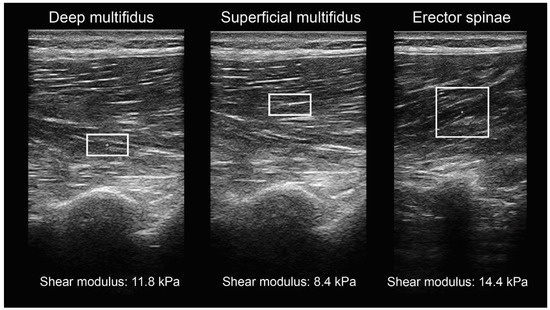

2.3. Shear-Wave Elastography